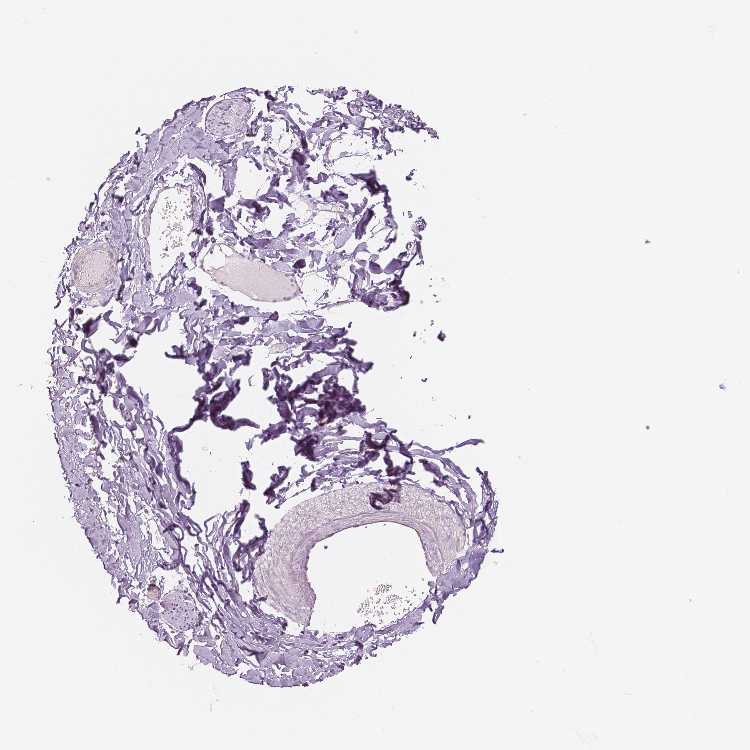

SOFT TISSUE 1 - Antibody stainingi

Antibody staining in the annotated cell types in the current human tissue is reported as not detected, low, medium, or high, based on conventional immunohistochemistry profiling in selected tissues. This score is based on the combination of the staining intensity and fraction of stained cells.

Each image is clickable and will lead to virtual microscopy that enables deeper exploration of all samples and also displays staining intensity scores, fraction scores and subcellular localization as well as patient and tissue information for each sample.

Antibody HPA008017

Fibroblasts Not detected

Peripheral nerve Not detected

SOFT TISSUE 2 - Antibody stainingi